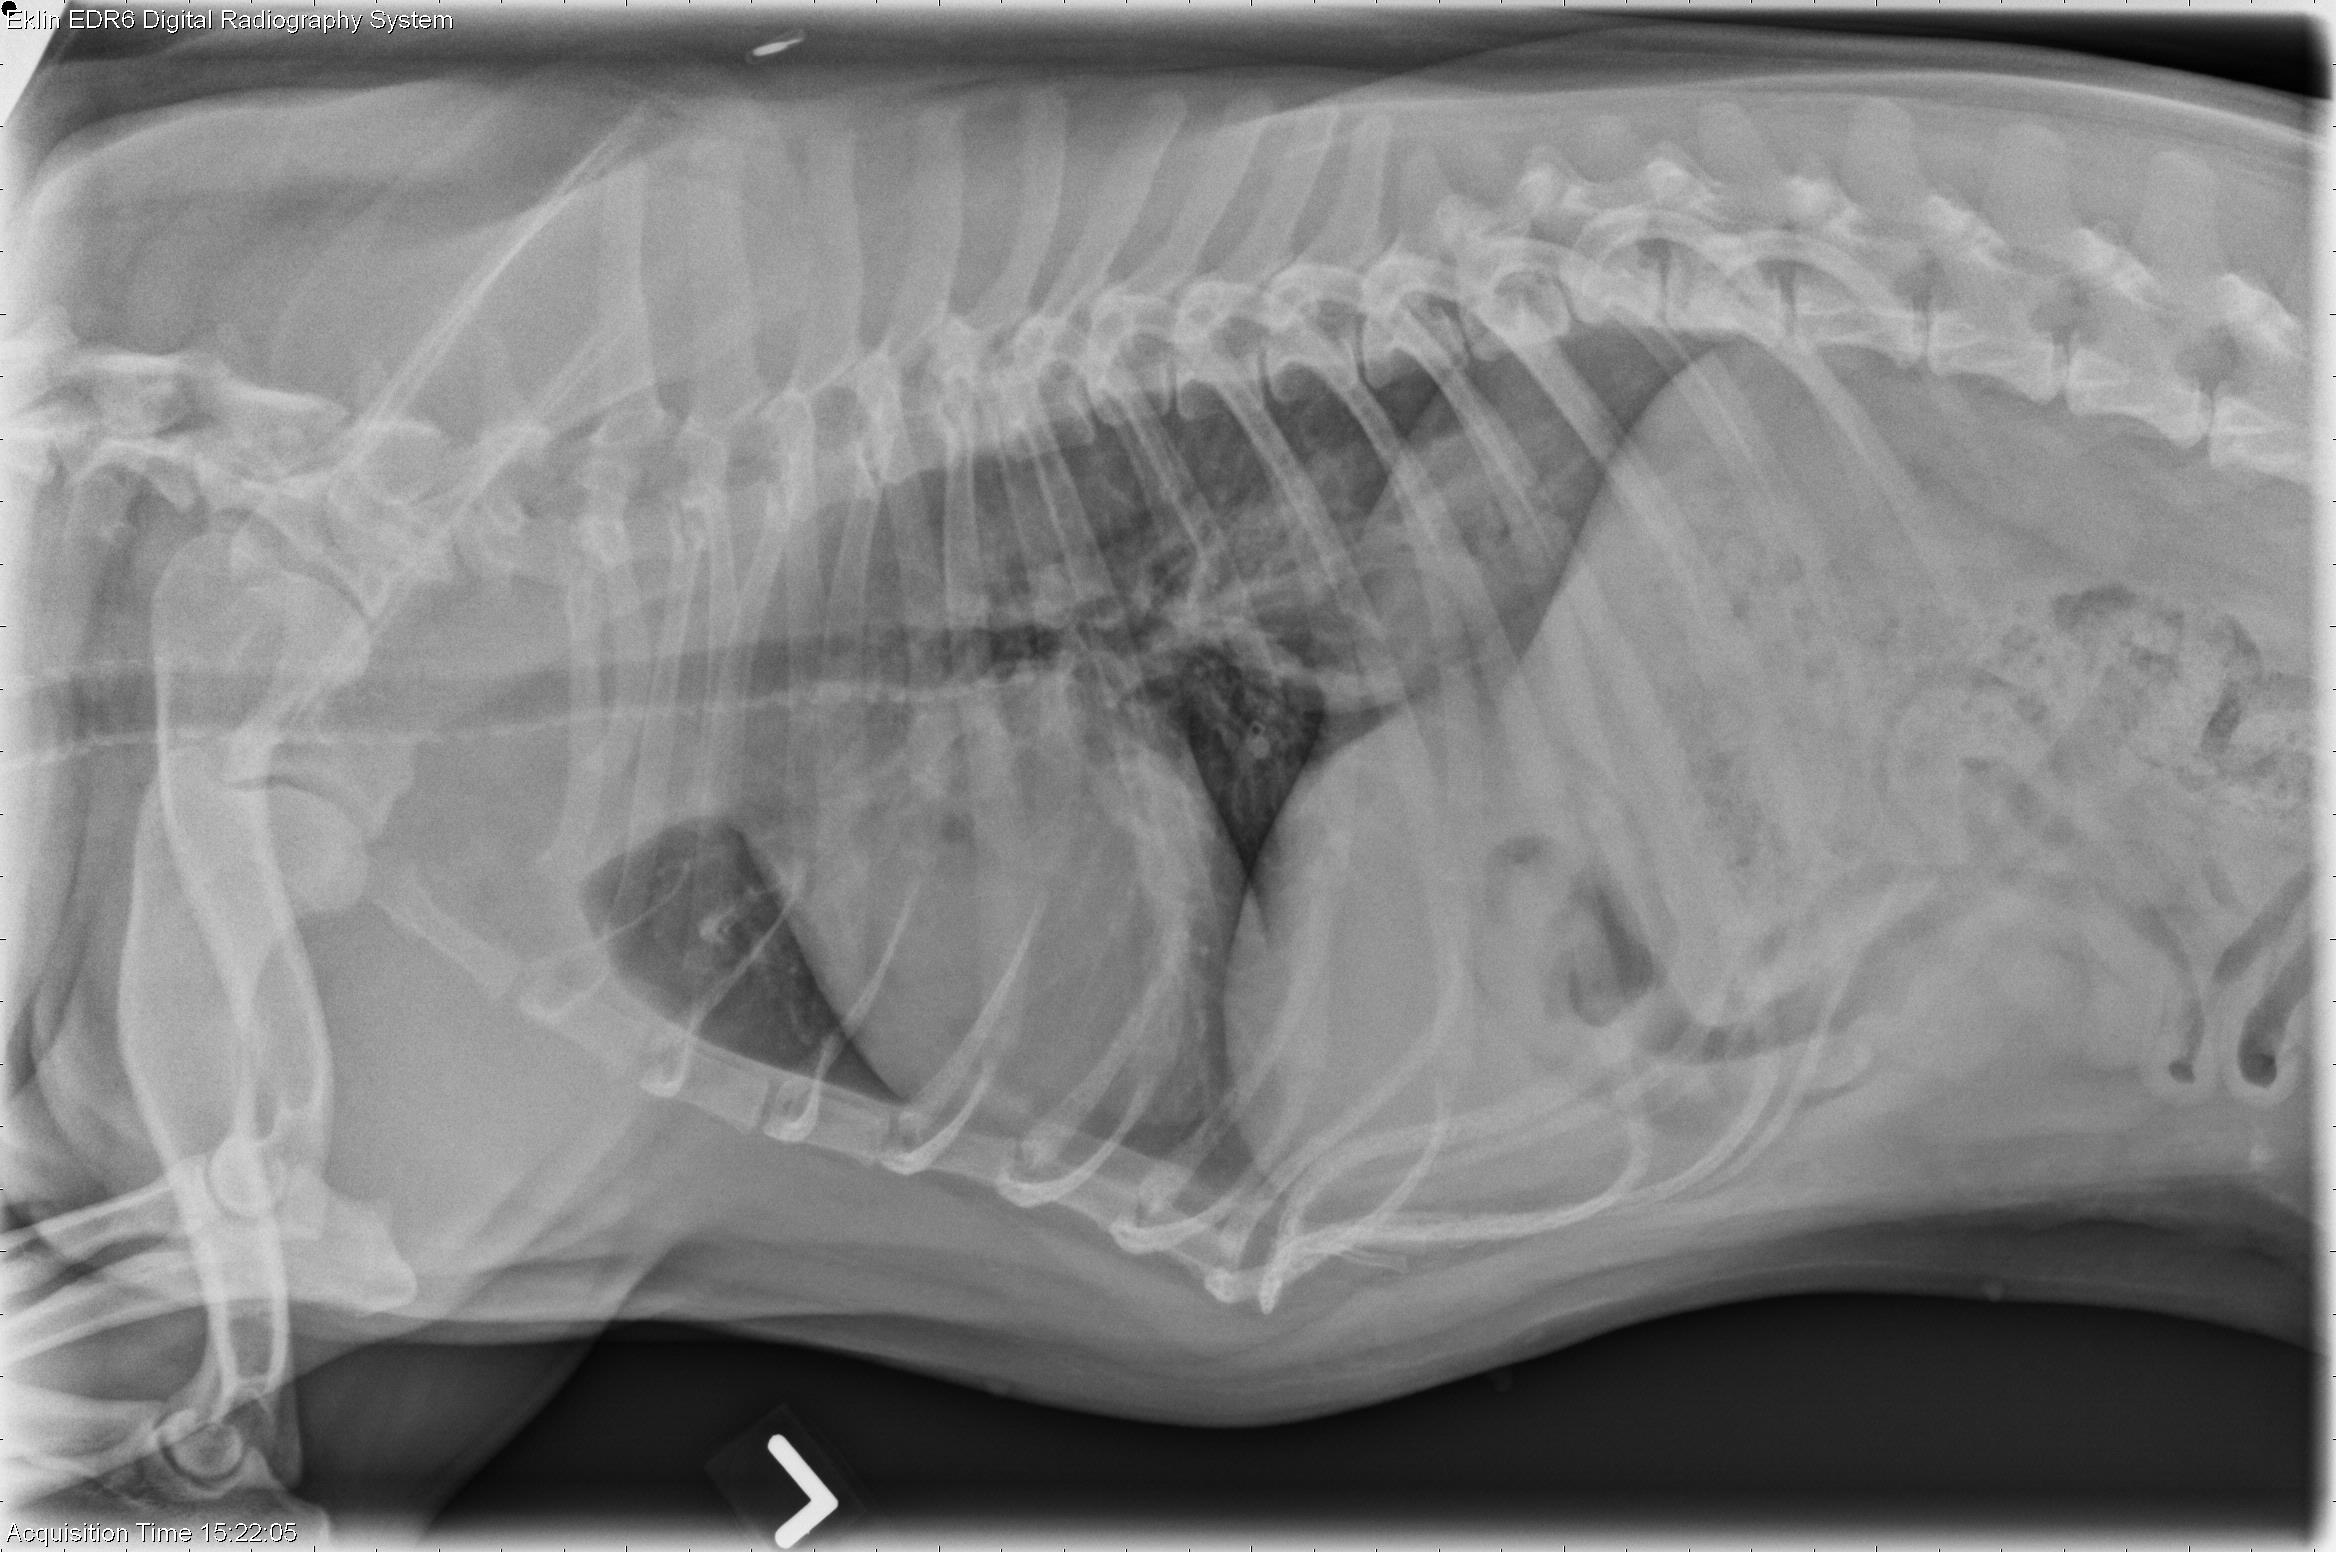

This week’s case is a 2-year-old male neutered French bulldog with central nervous system signs. These radiographs were taken prior to anesthesia.

The cardiovascular structures are normal in size and shape. The airways are patent. There is a broad-based soft tissue and gas opacity at the level of the diaphragm on the left lateral projection. The pleura and mediastinum are normal. Hemivertebrae are present in the thoracic spine, consistent with breed.

The intermittent soft tissue opacity in the region of the esophagus is most consistent with a sliding hiatal hernia, seen commonly in brachycephalic breeds.

• Sliding hiatal hernia (incidental, unlikely related to clinical signs)

• Inflammatory brain disease diagnosed on MRI